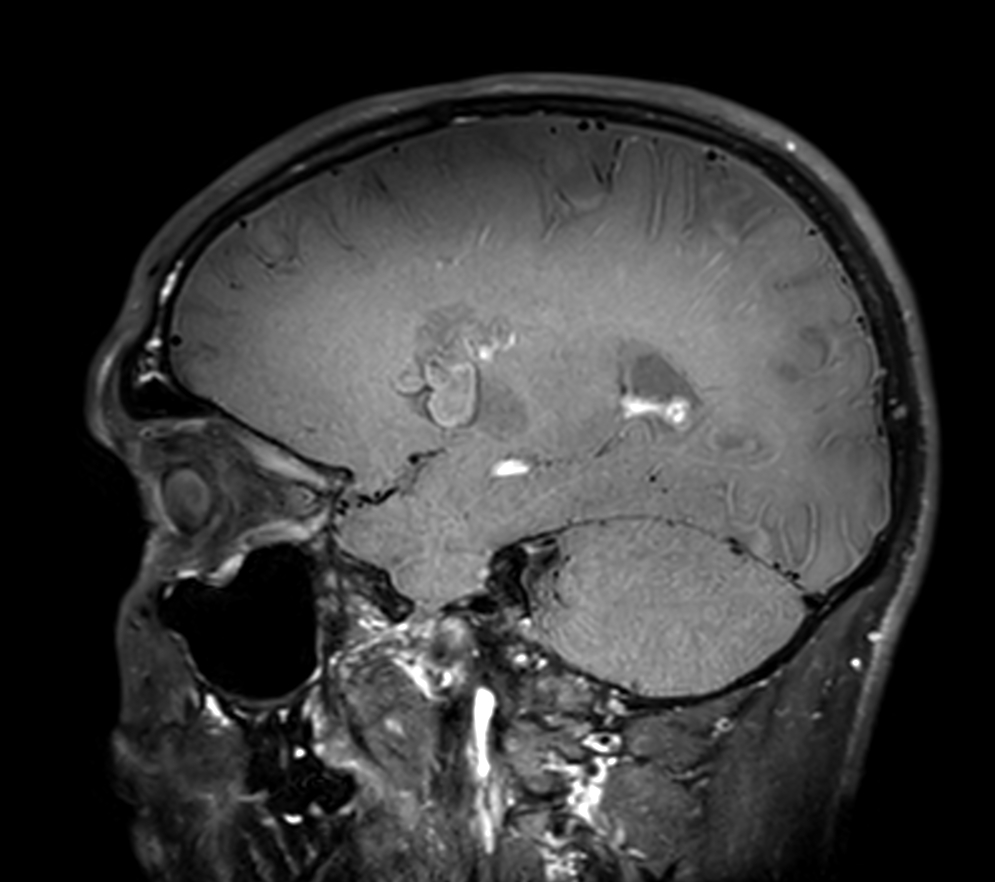

3D T1w TFE (post-gado)